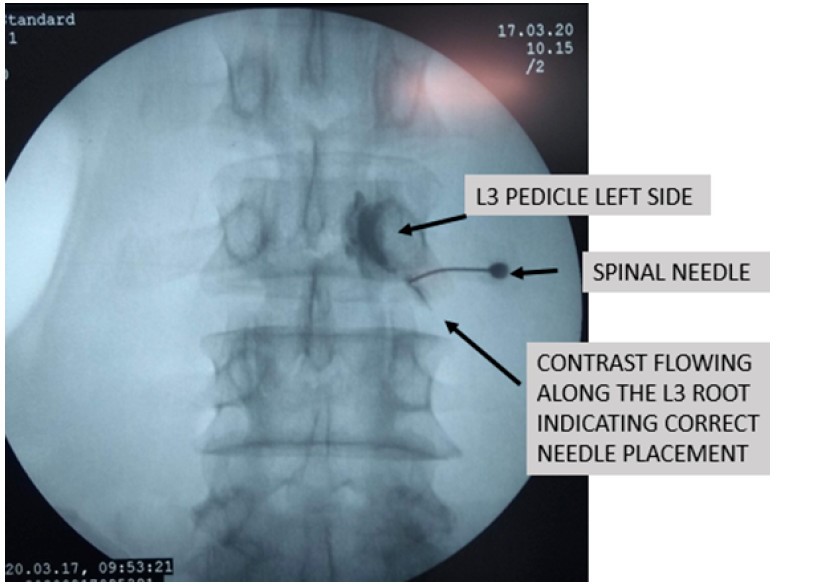

Thủ tục này là một phần của quản lý không phẫu thuật bên cạnh việc hỗ trợ chẩn đoán. Phong bế là hỗn hợp của thuốc gây tê cục bộ (bupivacaine 0,25% hoặc lignocaine 0,5%) và corticosteroid (triamcinolone axetat hoặc methylprednisolone) được phân phối ở mức mục tiêu (thoát vị đĩa đệm) dưới hướng dẫn của đèn huỳnh quang để giúp giảm đau cấp tính xuyên rễ bằng cách hành động gây mê và chống viêm.

+ Chỉ định cho SNRB bao gồm:

- Bệnh nhân thoát vị đĩa đệm chèn ép rễ nặng không muốn mổ

- Hình thái đĩa đệm không tương quan với triệu chứng lâm sàng: giúp khẳng định nguyên nhân gây đau vùng rễ là do thoát vị đĩa đệm hay do nguyên nhân nào khác

- Dự đoán kết quả: bệnh nhân thoát khỏi SNRB sẽ có kết quả thuận lợi nếu được điều trị bằng phẫu thuật.

- Đau tứ chi không điển hình: Một mũi tiêm ngoài màng cứng hoặc SNRB giúp giảm đau trong thời gian ngắn khoảng 3 tháng. Người ta đã chứng minh rằng bệnh nhân có thể trì hoãn cuộc phẫu thuật của mình trong vài năm nếu họ đáp ứng tốt với SNRB hoặc phong bế ngoài màng cứng. Một bệnh nhân có thể tiêm tối đa trong một năm. Mỗi lần tiêm phải cách nhau 1-2 tuần.